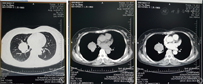

女性,51岁。因"咳嗽、咳痰"1周,于2015年11月28日收入广东医科大学附属深圳南山医院呼吸科。患者咳嗽以刺激性干咳为主,少量黏白痰。无咳血,无发热、盗汗,无体重减轻。门诊治疗无好转,行胸部X线片提示右肺门区占位性病变,遂行胸部CT平扫及增强表现:右肺中叶、下叶支气管间可见一类圆形肿块,直径约4.2 cm,密度较均匀,CT值约为36 Hu,动脉期CT值约80 Hu,实质期约90 Hu,考虑偏良性病变(硬化性血管瘤、孤立性纤维瘤),不完全排除类癌(图1)。既往有子宫肌瘤和胆囊结石病史。体格检查:神清,无贫血貌,全身皮肤、巩膜无黄染,浅表淋巴结未触及肿大,口唇无发绀,颈软,胸廓无畸形,双肺语颤增强及减弱,双肺叩诊清音,双肺呼吸音清,未闻及干湿性啰音。心前区无隆起,无震颤,心界无扩大,心率93次/min,律齐,未闻及杂音。腹平软,全腹无压痛,无反跳痛,肝脾肋下未触及,莫菲氏征阴性,肝肾区叩痛阴性。双下肢无水肿。入院后积极完善各项检查:血、尿、粪常规正常。红细胞沉降率为56 mm/h,C反应蛋白(C reactive protein,CRP)12.7 mg/L,糖类抗原CA153为41.76 IU/ml ,痰找抗酸杆菌、结核感染T细胞、γ-干扰素(interferon-γ,IFN-γ)三项检测均阴性。支气管镜检查提示右中叶、右下叶基底段外压性狭窄。考虑位于肺门,位置深,穿刺活检困难,遂经本科会诊后转入手术治疗,12月3日全麻双腔气管插管胸腔镜下行右肺门肿物切除,术中见水平裂与斜裂交界处约5 cm×4 cm大小圆形肿块,予以吸引器、超声刀钝锐性分离,肿瘤内侧与肺动、静脉关系密切,血供丰富,有滋养血管,紧贴右中、下叶支气管分叉处完整切除,术中冰冻病理考虑良性肿瘤,未做纵隔淋巴结清扫,术后常规病理见肿瘤为实性、乳头状、硬化性和出血性组织结构混合,增生的Ⅱ型肺泡细胞被覆在乳头状结构表面,并可见慢性炎症和泡沫细胞等变化(图2)。免疫组织化学检查明确为硬化性血管瘤(图3),术后恢复顺利,第8天痊愈出院。随访11个月,患者无不适,复查胸部CT未见异常。